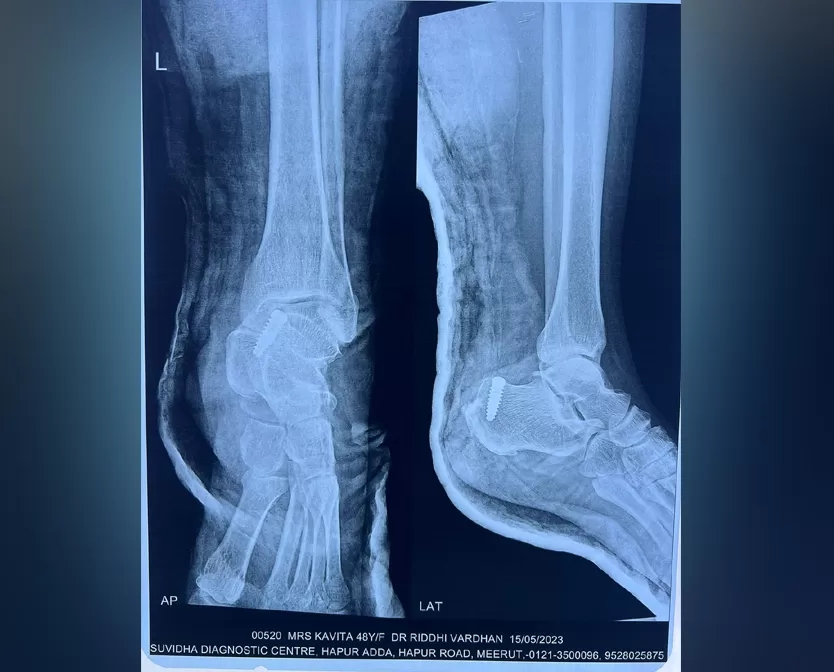

Mrs. Kavita

Name: Mrs. Kavita

Date of Operation: 15 May 2023

Age: 45 Years